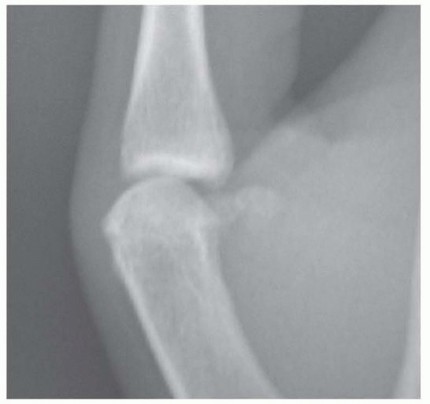

Standard radiographic evaluation is mandatory for all suspected collateral ligament injuries. This includes true posteroanterior (PA), lateral, and oblique views of the injured thumb. It is highly recommended to obtain comparative views of the uninjured contralateral thumb to assess baseline joint congruency and identify subtle anatomical variations.

Radiographs are scrutinized for the presence of avulsion fractures at the ligament insertions (the "bony gamekeeper's" thumb), volar subluxation of the proximal phalanx, or pre-existing degenerative changes. While stress radiographs were historically popular, they are often intensely painful for the patient and rarely alter the treatment plan if a thorough clinical exam has been performed; however, they can be utilized under local anesthesia if the clinical exam is equivocal.

Advanced imaging modalities, such as Magnetic Resonance Imaging (MRI) or high-resolution ultrasonography, are excellent tools but are not strictly required for every acute injury. MRI is highly sensitive and specific for identifying complete ligament ruptures and the classic "yo-yo on a string" appearance of a Stener lesion. Ultrasound, when performed by an experienced musculoskeletal radiologist, offers the advantage of dynamic, real-time assessment of ligament integrity during stress maneuvers. These modalities are most useful in complex cases, delayed presentations, or when the clinical examination is limited by severe swelling and guarding.